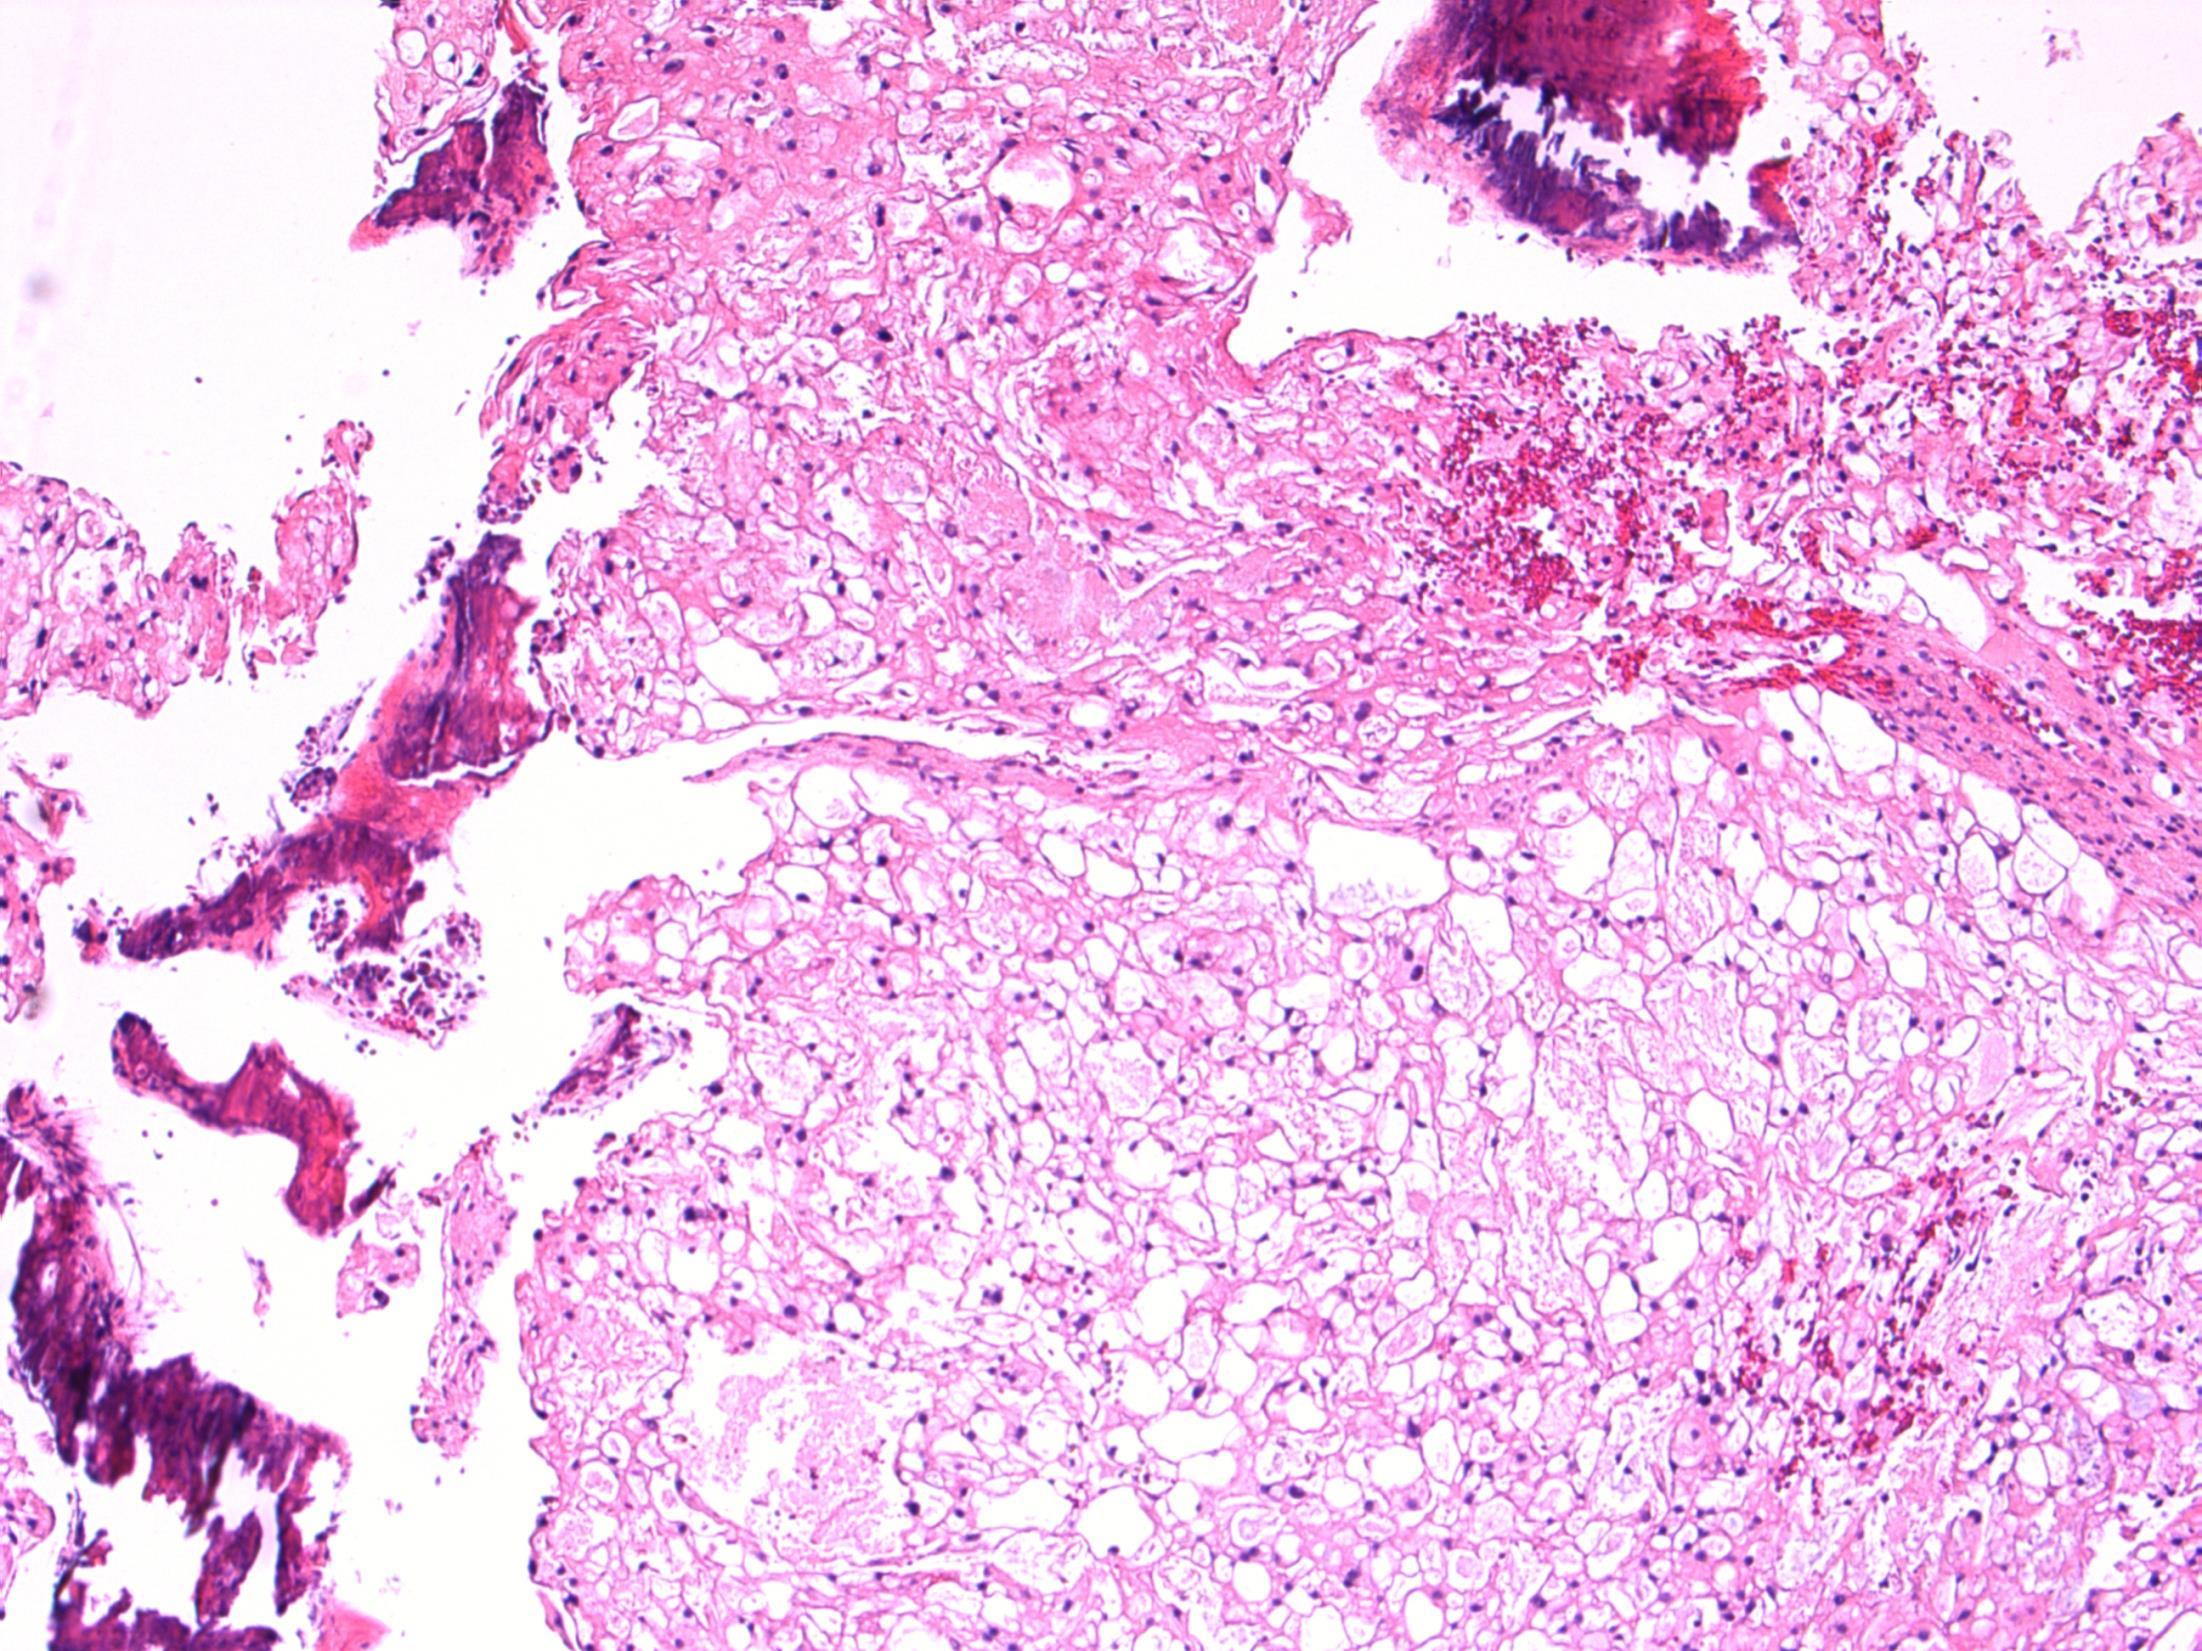

Massive ovarian oedema

Description: Diffuse oedema of medulla and inner cortex; relative sparing of outer cortex. Associated RBC extravasation, congestion, inflammation. No cyst seen. No evidence of malignancy.

Diagnosis: Massive ovarian oedema

Differential Diagnosis:

• Fibroma/ fibrothecoma. May show marked oedema but tumour usually replaces entire ovary with no sparing at edges.

• Krukenberg tumour. Can look similar macroscopically and malignant cells can be sparse. Usually older females but can occur in younger females.

Plan:

• Extra blocks to exclude sparse tumour cells.

• Correlate with radiology.

Comments:

Partial torsion of an otherwise normal ovary.

Common in 2nd and 3rd decade – like this case.

Macroscopically a featureless myxoid enlarged ovary (correlates with macro features).